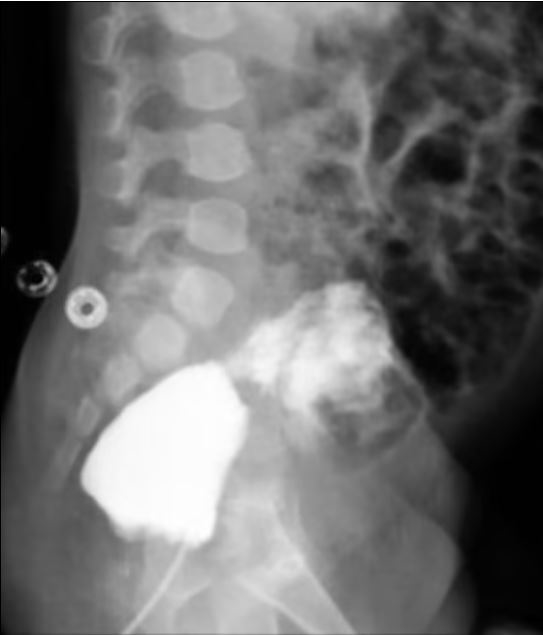

Özel bir boya ile mesane ve rektum arasındaki işlev incelendiğinde, bu iki organ arasında anormal bir bağlantı sağlayan bir fistülün bulunduğu belirlendi. Günümüzdeki cerrahlar ise; "falloplasti" ameliyatı adı verilen bir prosedürle, bu şartlar altında doğan erkek bebeklere yapay şekilde genital organları yapılıyor. Ayrıca Doktorların üriner sistemlerini tekrar birbirine bağlamasıyla onlara bir üretra da verilebilir.